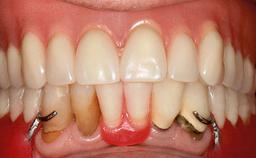

A healthy 28-year-old female patient presented for a consultation on treatment options to restore her upper right central incisor. At the clinical examination, the tooth responded to percussion and palpation. The gingiva was red and slightly swollen, with a mid-facial probing depth of 10 mm. The upper right lateral incisor showed no signs or symptoms, did not respond to exploration and percussion, and the vitality test was positive. The periapical radiograph revealed that tooth 11 had been endodontically treated, with no lesion evident at the apex. A small radiopaque calcified structure surrounded by a narrow radiolucent zone (3 × 3 mm) was present at the apex of tooth 12.